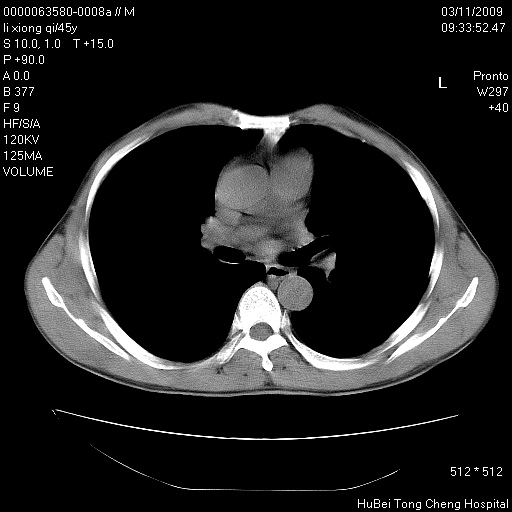

患者 男,45岁。胸痛,咳嗽伴痰中带血1月余。

临床诊断:肺结核?

胸部ct轴位平扫(层厚10mm,螺距1.5,重建间隔10mm),图像如下:

考虑肝癌肺转移